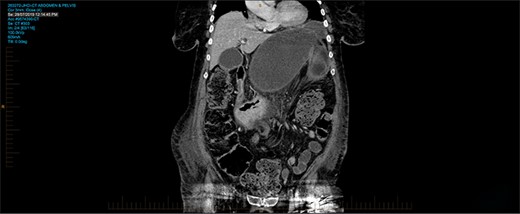

A 93-year-old patient who has history of recurrent sigmoid volvulus presented with a week of abdominal distension and bowels not working. Initial blood test revealed that she has white cell count 11.3 × 109/L, CRP 12 and lactate of 1.9. CT abdomen was performed on admission showed features of sigmoid volvulus. Patient was booked for flexible sigmoidoscopy to decompress the sigmoid volvulus. Flexible sigmoidoscopy revealed that there was significant mucosal necrosis of the sigmoid colon. A diagnostic laparoscopy was performed to determine the severity of necrosis. Laparoscopy reported that the sigmoid colon was oedematous but no signs of transmural necrosis. Patient was kept in the hospital for observation but there were no signs of improvement. Day 4 of the admission, patient continues to deteriorate clinically and had a medical emergency team response call for worsening pain and hypotension, and a repeat CT abdomen was performed. The images were consistent with sigmoid volvulus through transmesocolon defect resulting an internal hernia (Figure 5–7). The patient had emergency laparotomy. The sigmoid colon was found to be in the supracolic compartment and required decompression prior to reduction (Figure 1–4). There was transmural necrosis close to the rectosigmoid junction. Patient underwent Hartmann procedure. Patient recovered well postoperatively and discharged to home.

CT on coronal view showing sigmoid colon in the supracolic compartment.